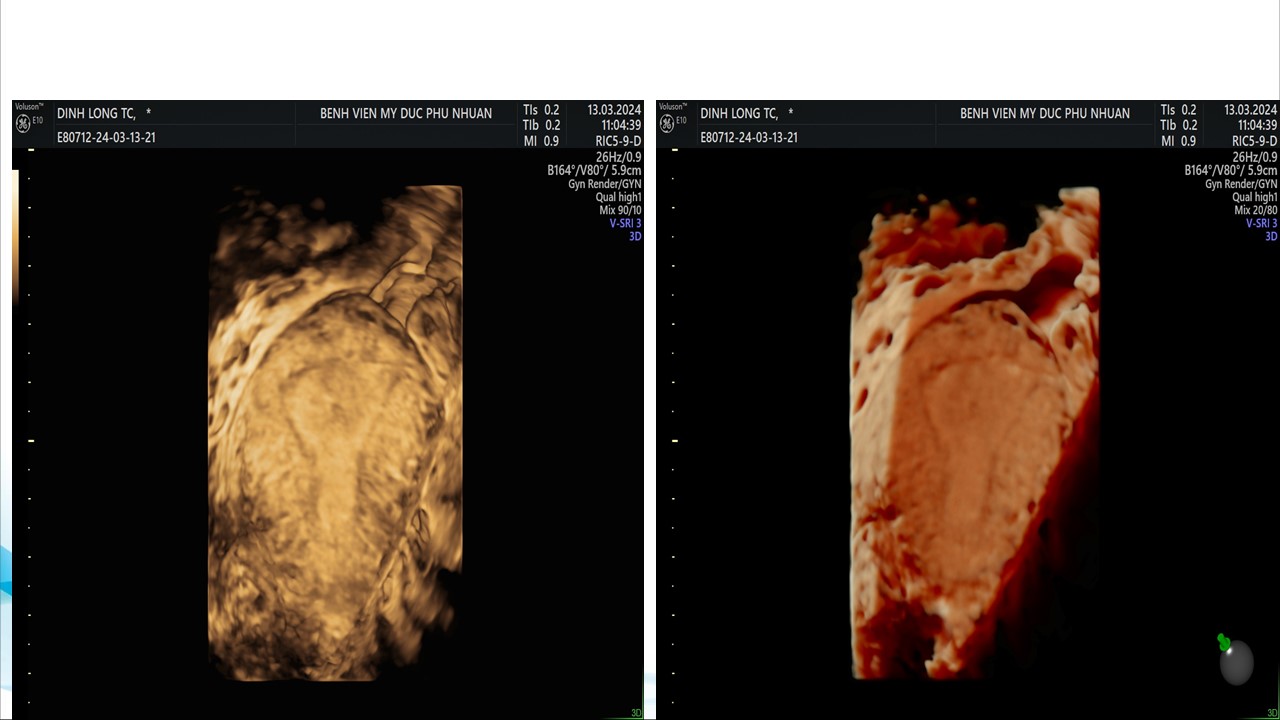

Siêu âm sử dụng chật tương phản trong phụ khoa

BS. CKI Phạm Thị Phương Anh - Bệnh viện Mỹ Đức